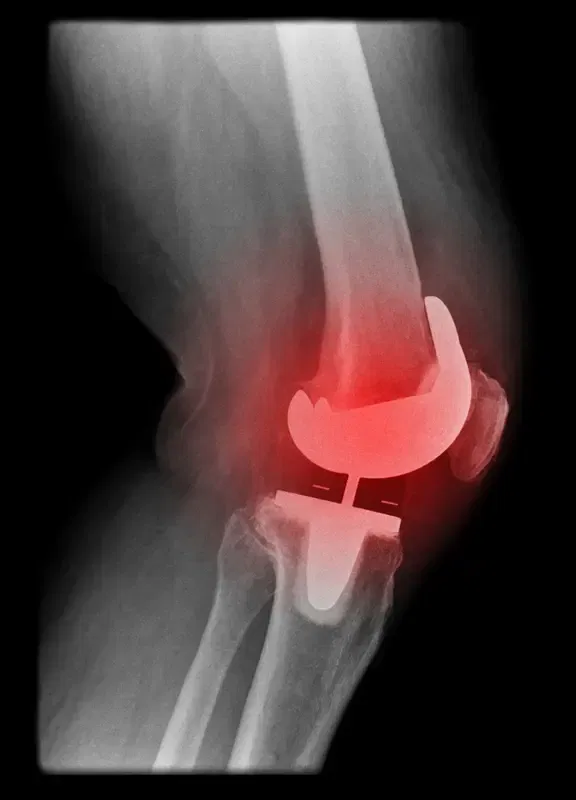

Modular femoral component with a long stem

Revision knee replacement may require the use of special implants with attachments for stem and bone augments. The modularity of these implants helps the surgeon to achieve far greater stability than traditional implants.

Modular tibial tray with metal bone augments